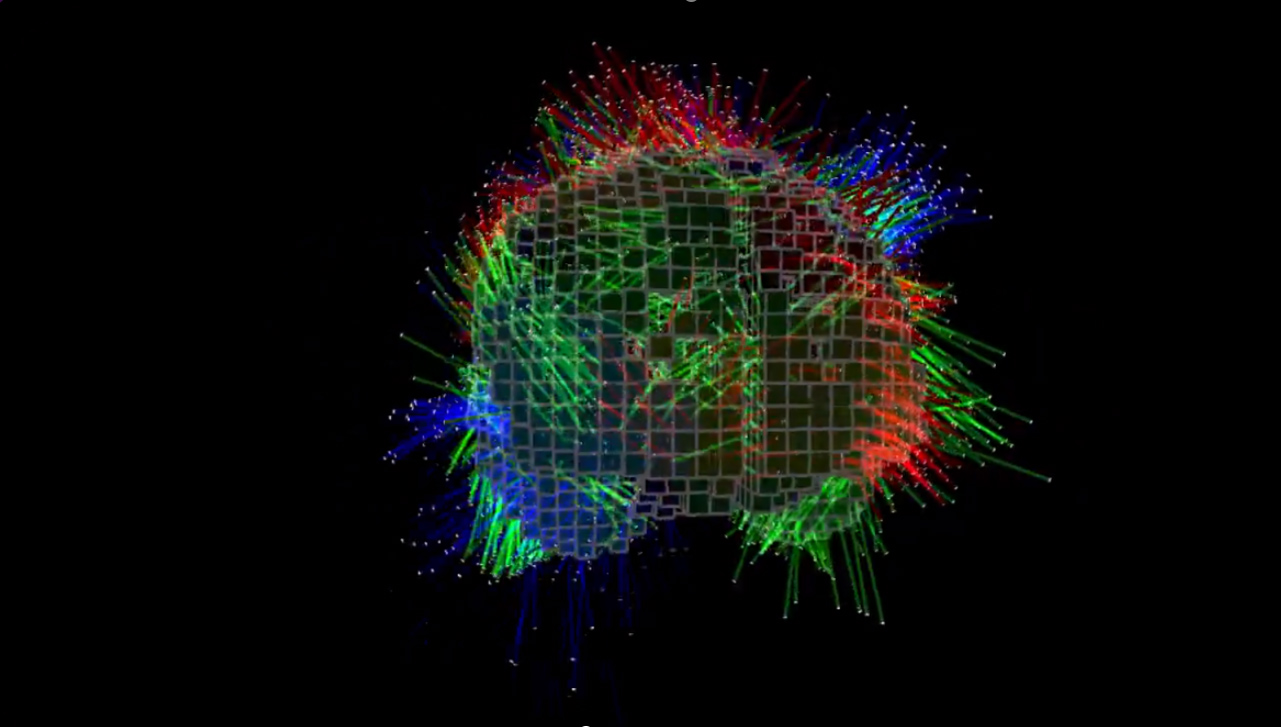

7. 脑部电子活动的3D显示:

2014年,与 STM Holography 和 Cerebral Diagnostics 合作,实验室开发了在睡眠期间捕捉和显示大脑电子活动的3D视图技术。

2014 年,STM Holography and Cerebral Diagnostics 与 PHASE Lab 合作开发技术,以捕捉和显示睡眠期间大脑电子活动的 3D 视图。 「我们的研究重点是以商业标准 3D 格式创建大脑模型,然后将其整合到标准化全息图列印格式中,」佩奇说。 “Cerebral Diagnostics 希望能够将动画视频全息图通过FTP 传输到他们的服务局。” PHASE ab 取得了Cerebral Diagnostics 创办人兼执行长Mark Doidge 博士记录的资料集,并努力将其准确地转化为PHASE Lab 和STM Holography 商业服务局的全像印表机的「相机就绪艺术品」。 Page 表示,“这些全像图不仅以 3D 形式表示数据,还传递大脑电活动随时间变化的数据变化。”佩奇说,这项研究「领先于时代」。

脑电活动全息图|图片由 PHASE 实验室提供

- 大脑电子活动捕捉与显示:2014 年与 STM Holography and Cerebral Diagnostics 合作,研究在睡眠期间大脑电子活动的 3D 视图捕捉与显示技术。

实验室的目标是探索大脑活动如何与梦境和其他夜间过程相关联,最终创造出一种可以将脑电活动可视化的3D全息图。」佩奇解释道。这项合作不仅展示了全息技术在医学领域的潜力,还揭示了大脑研究新的可能性。